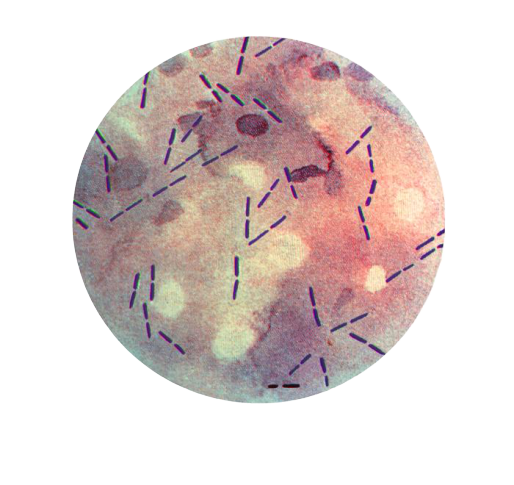

Direct Microscopy

Gram-stained smears of aspirated material from myonecrosis reveal a necrotic background with a lack of inflammatory cells and presence of gram-positive bacilli with a morphology resembling C. perfringensor other clostridia. Gram stained films provide clues about the species of clostridia present.

- Thick, stubby, boxcar-shaped, gram-positive bacilli without spore are suggestive of *C. perfringens.*The cells of C. perfringensare usually 0.8 to 1.5 ÎĽm in diameter Ă— 2 to 4 ÎĽm long and have blunt ends. They are often described as boxcar-shaped.

- Spore bearing gram-positive bacilli suggest other clostridia species

Citron bodies (boat or leaf-shaped) pleomorphic irregularly stained bacilli with spores suggest C.septicum. Large rods with oval sub-terminal spores- suggest C. novyi